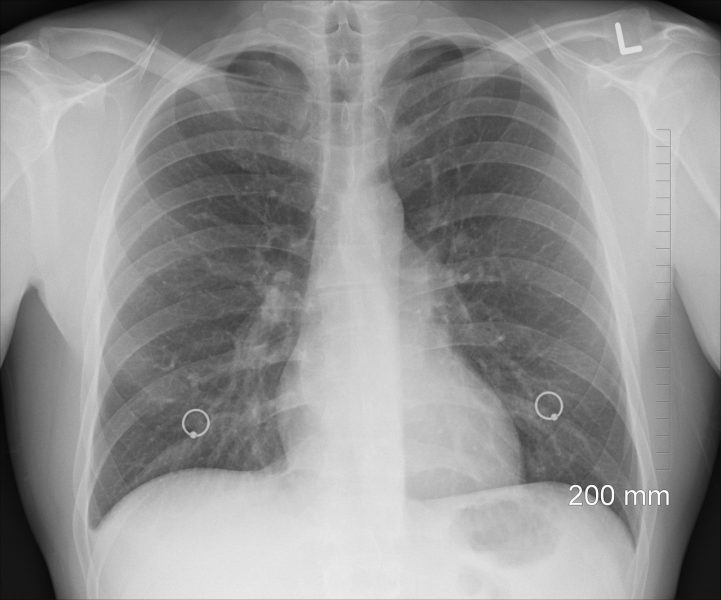

Для постановки диагноза потребуется сбор анамнеза, физикальный осмотр, а также ряд лабораторных исследований, например, посев мокроты на микрофлоры с определением чувствительности к антибиотикам и микроскопией мазка, общий анализ мокроты, общий анализ крови.